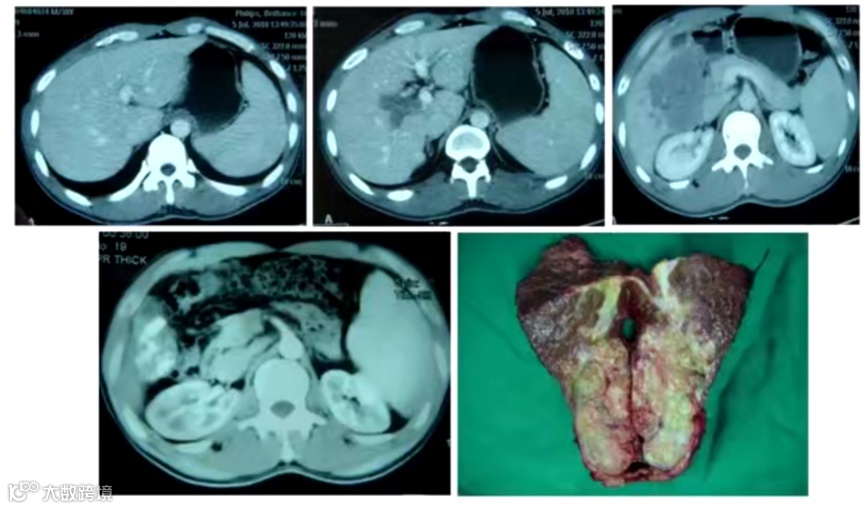

3)病例三:伴门脉主干癌栓肝细胞癌患者经靶向联合TACE转化切除。如图3所示,一例伴门脉主干癌栓肝细胞癌患者经仑伐替尼联合TACE治疗3个月后,甲胎蛋白332ng/ml降到49ng/ml;异常凝血酶原1486μg/L降到344μg/L;左肝癌缩小,门脉癌栓明显回缩。随后进行左半肝及尾叶切除,至今仍在随访中。

图3. 伴门脉主干癌栓肝细胞癌患者经靶向联合TACE转化切除